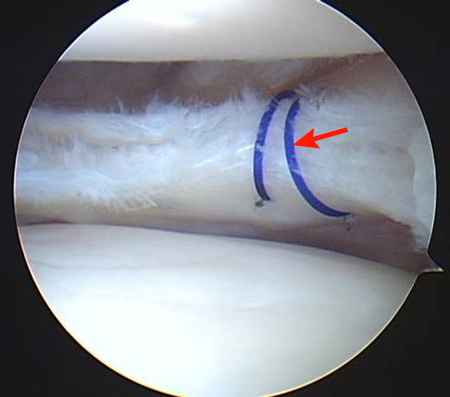

Arthroscopic view of suture repair of lateral meniscus (arrow)

From the collection of Dr Kevin R. Stone